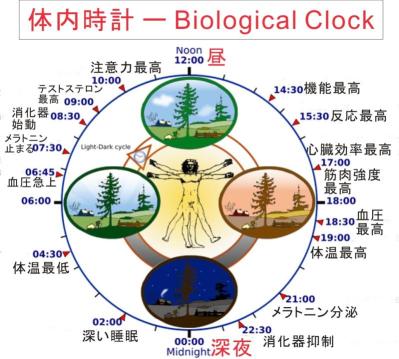

眠くなるのは脳神経の一部がホルモン(メラトニン)を分泌し、血液で体中に巡回し「休憩時間」だと告げる--下画像参照

熟睡時間に体の方は自律神経で動き続き、脳は体との交信を減らし、1日の疲労から回復し再生・情報整理をする。

この期間に脳は毎日の修理・保守、起きていた時の経験・記憶・優先事項を記録し、次の日に備え免疫モルモン等を

生産している、と提案されている。